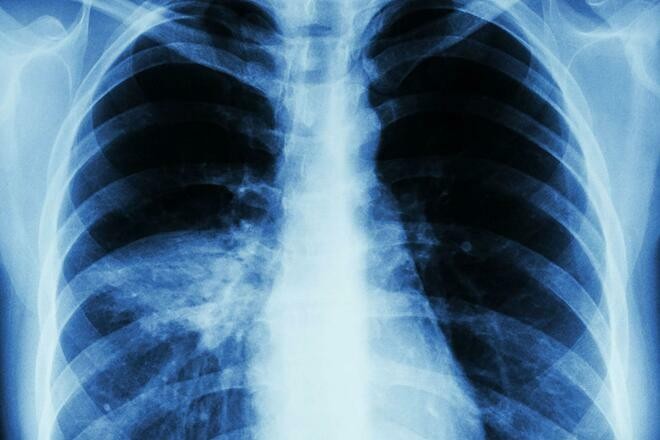

Viêm phổi là bệnh nguy hiểm, có thể dẫn tới tử vong. Ảnh: News.Virginia

Viêm phổi là viêm các phế nang trong phổi do một yếu tố gây bệnh nào đó gây nên, hay gặp nhất là vi khuẩn, virus hoặc vi nấm. Viêm phổi có thể ở một vùng hoặc một vài vùng (viêm phổi thùy hoặc "đa thùy") hoặc toàn bộ phổi.